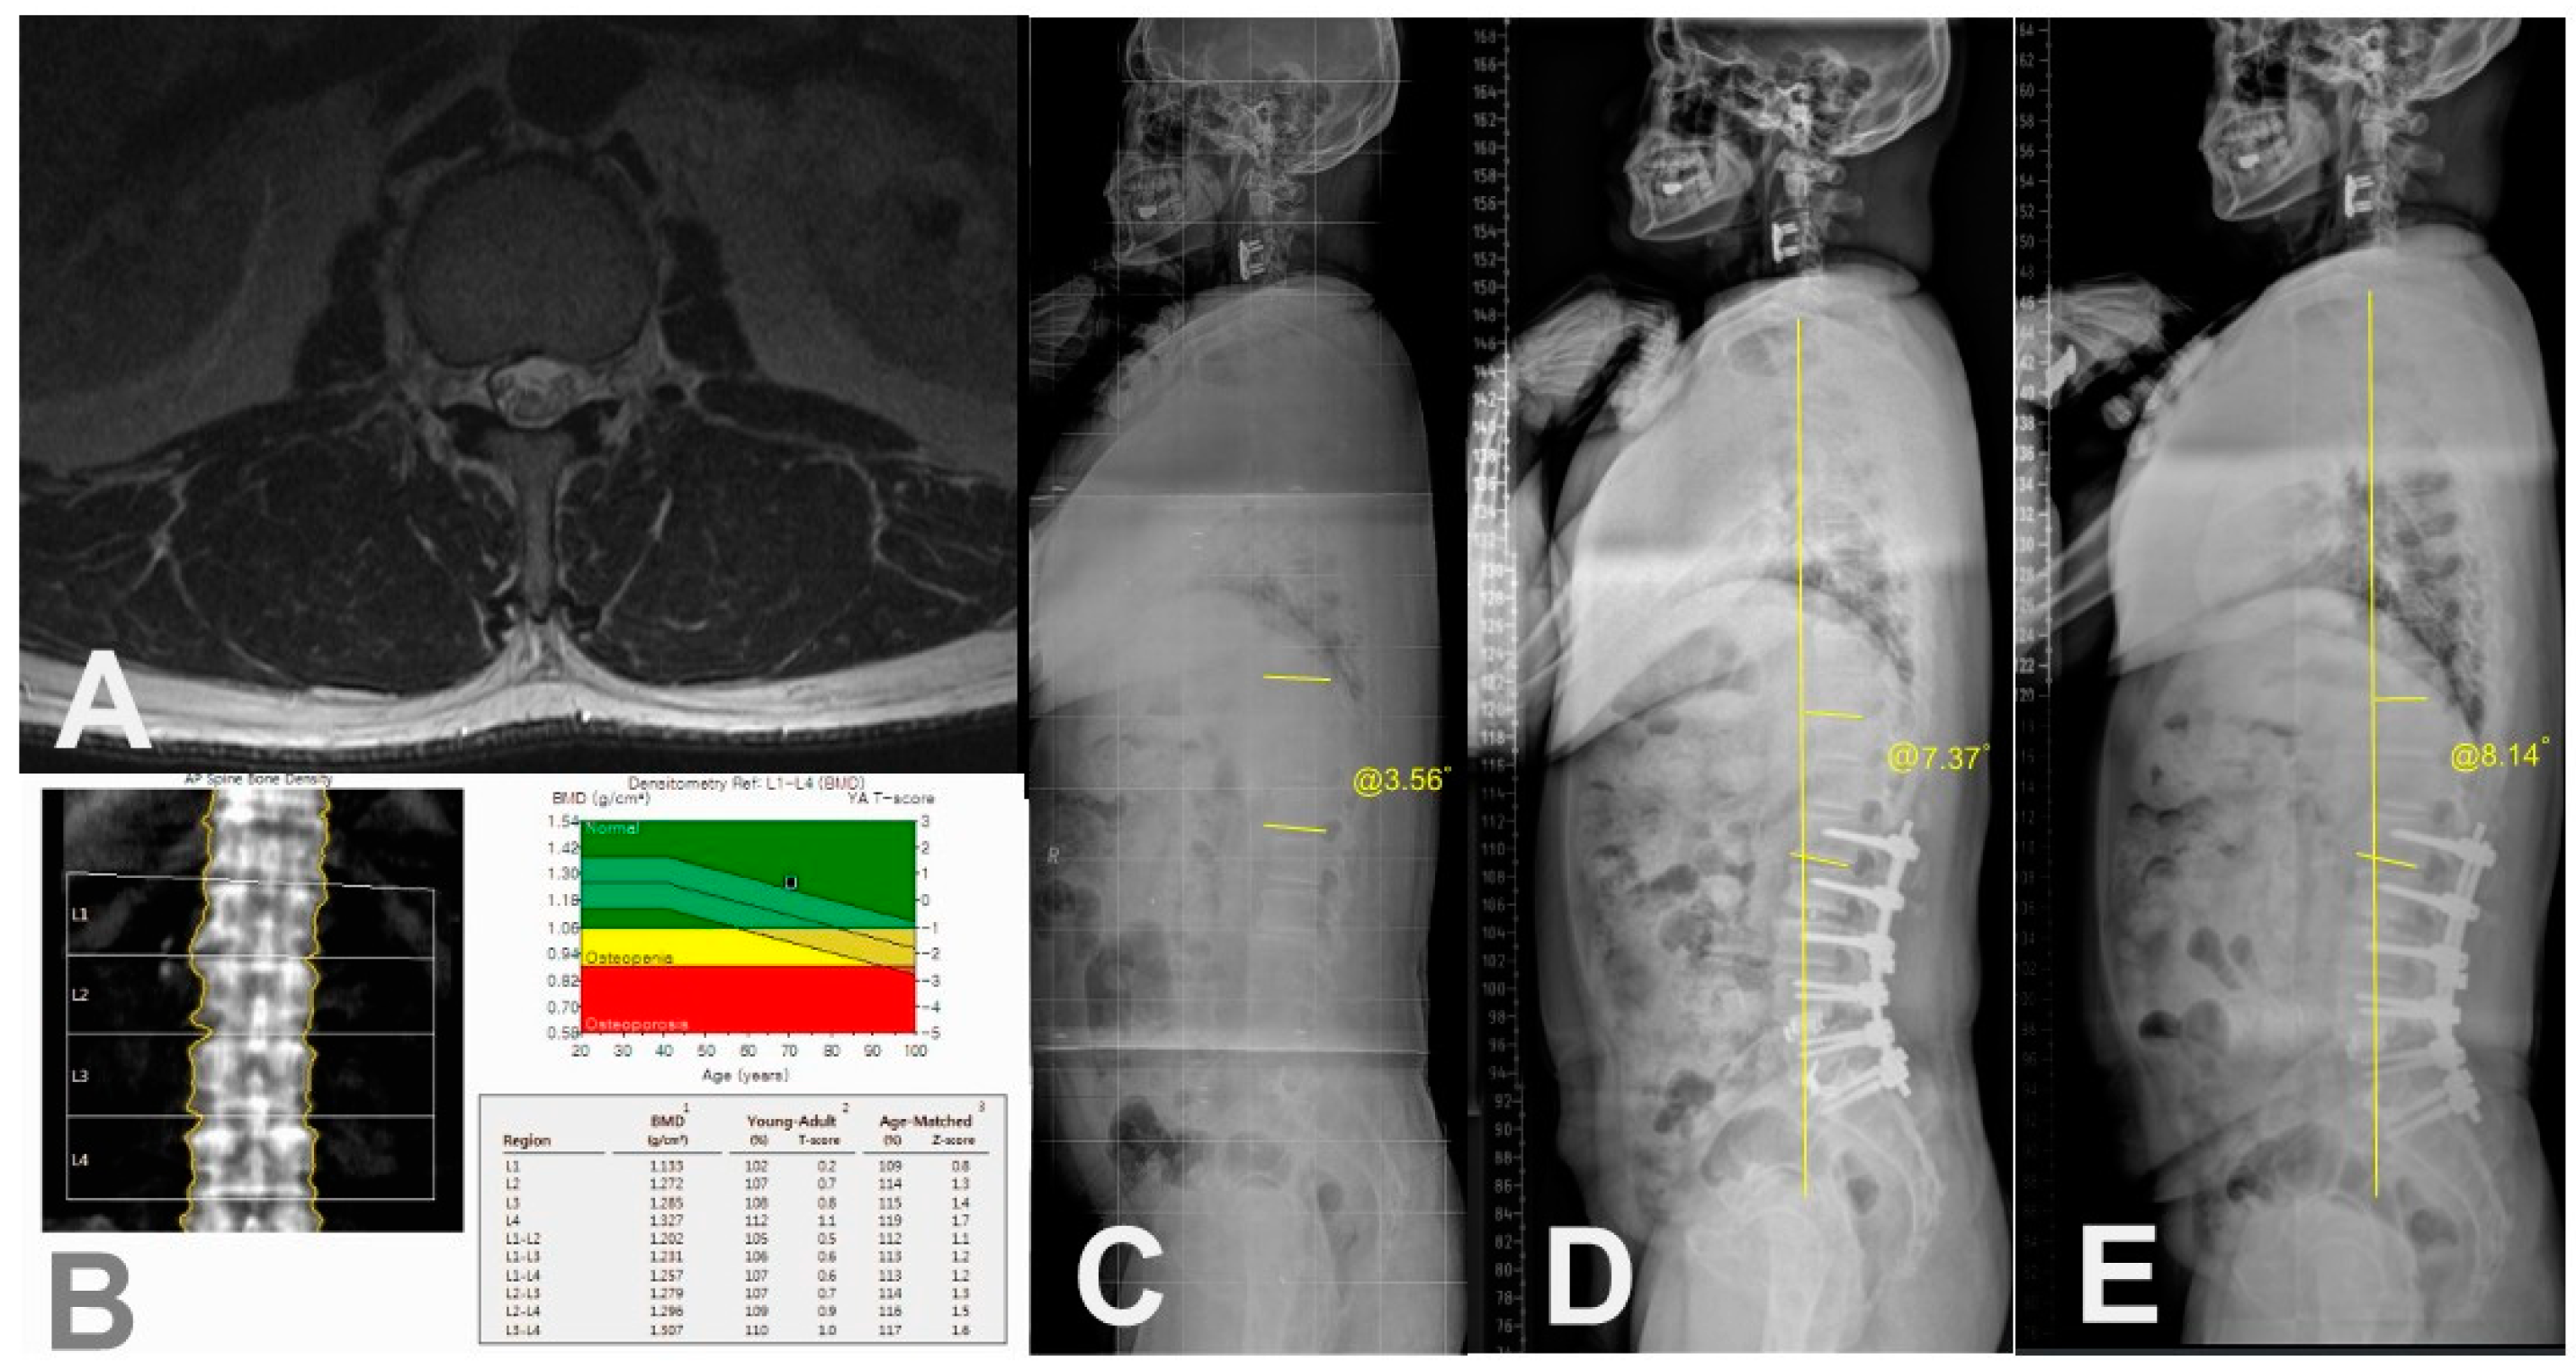

For radiographic assessment of spinopelvic parameters, standing 36-inch-long cassette AP and lateral radiographs of the whole spine were measured at the preoperative, the immediate postoperative, and the regular postoperative outpatient visits (3, 6, 9 months, 1-, 2-year and the final follow-up), respectively. On the radiographs, C7 sagittal vertical axis (C7SVA), thoracic kyphosis (TK) [18], thoracolumbar kyphosis (TLK) [18,19], lumbar lordosis (LL) [18], sacral slope (SS) [18], pelvic tilt (PT) [18], pelvic incidence (PI) [18,19,20] and proximal junctional angle (PJA) were measured (Figure 2). We also collected and analyzed the change (preoperative minus postoperative) of each radiographic parameter between the preoperative and the immediate (3 months) postoperative.

Figure 3. Measurement of Sagittal Spinopelvic Parameters.

Figure 4. A case of 66-year old female patient with PJK. A) Preoperative axial T2-weighted magnetic resonance image showing erector spinae muscle with severe (>50%) fat infiltration at T12-L1 level. B) Preoperative BMD showing osteoporosis. C) Preoperative whole spine standing lateral radiograph showing PJA of 5.37˚. D) Postoperative 3-month standing lateral whole spine radiograph showing PJA of 10.42˚. E) Postoperative 2-year standing lateral whole spine radiograph showing PJK (PJA of 28.17˚) with increased C7SVA.

Figure 5. A case of 73-year old female patient without PJK. A) Preoperative axial T2-weighted magnetic resonance image showing erector spinae muscle with minimal fat infiltration at T12-L1 level. B) Preoperative BMD showing no osteoporosis C) Preoperative whole spine standing lateral radiograph showing PJA of 3.56˚. D) Postoperative 3-month whole spine standing lateral radiograph showing PJA of 7.37˚. E) Postoperative 3-year standing lateral whole spine radiograph showing PJA of 8.14˚ with maintained C7SVA.